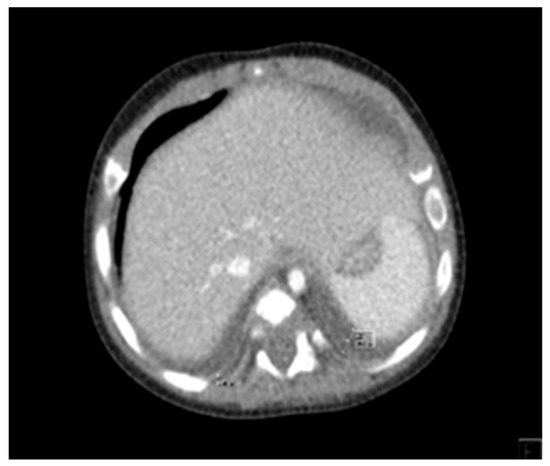

2. Case Report